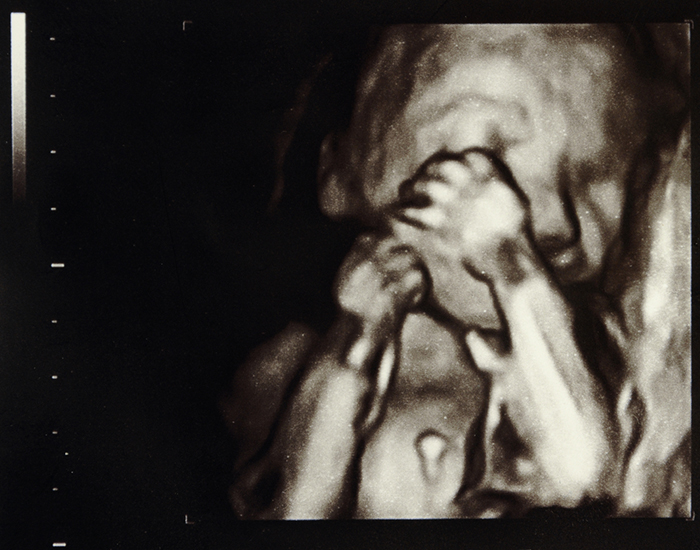

23 Haftalık Bebek Görüntüsü

23 Haftalık Gebelik Ultrason Görüntüleri

Her 23 haftalık bebek ultrason görüntüsü buradakiyle aynı olmak zorunda değil. Dolayısıyla ultrasonundaki farklılıklar seni endişelendirmesin, bebeklerin anne karnındaki duruşları ve hareketlerinin farklı olması gayet normal.